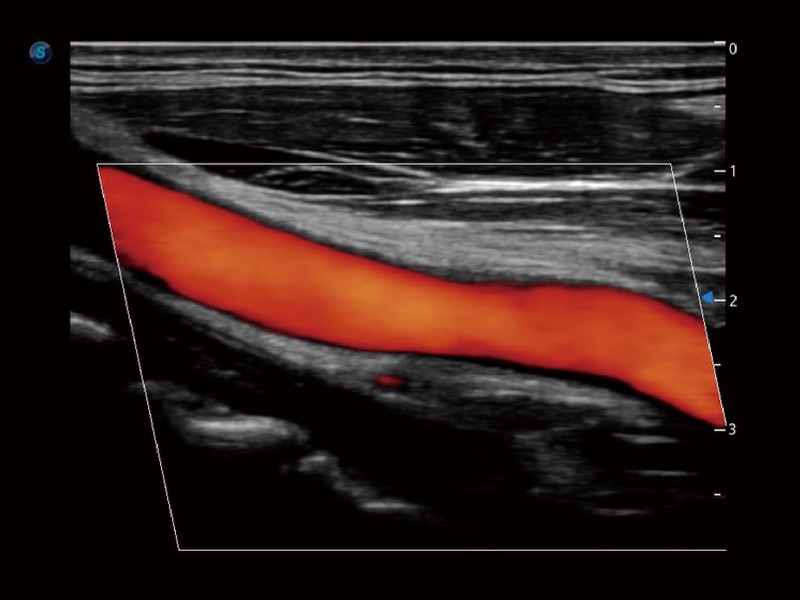

高分辨率血流成像技術(shù)提高了對低速血流信號(hào)的檢測能力。在提高空間分辨率的同時(shí),也克服了血流外溢現(xiàn)象,為用戶提供更加真實(shí)的血流動(dòng)力學(xué)信息。